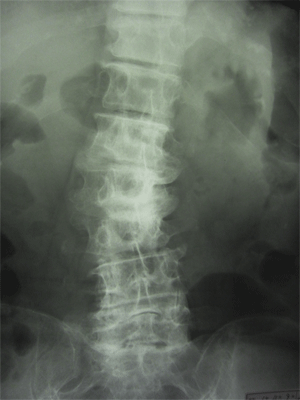

• 変形性腰痛症

変形性腰痛症は腰椎の加齢変化により腰痛が起こる診断名で、特に臨床症状の上で特徴的な識別点はありません。

椎間板の変性、椎体や椎間関節の変形、脊柱起立筋の疲労などが重なり合って発症するものを言う。